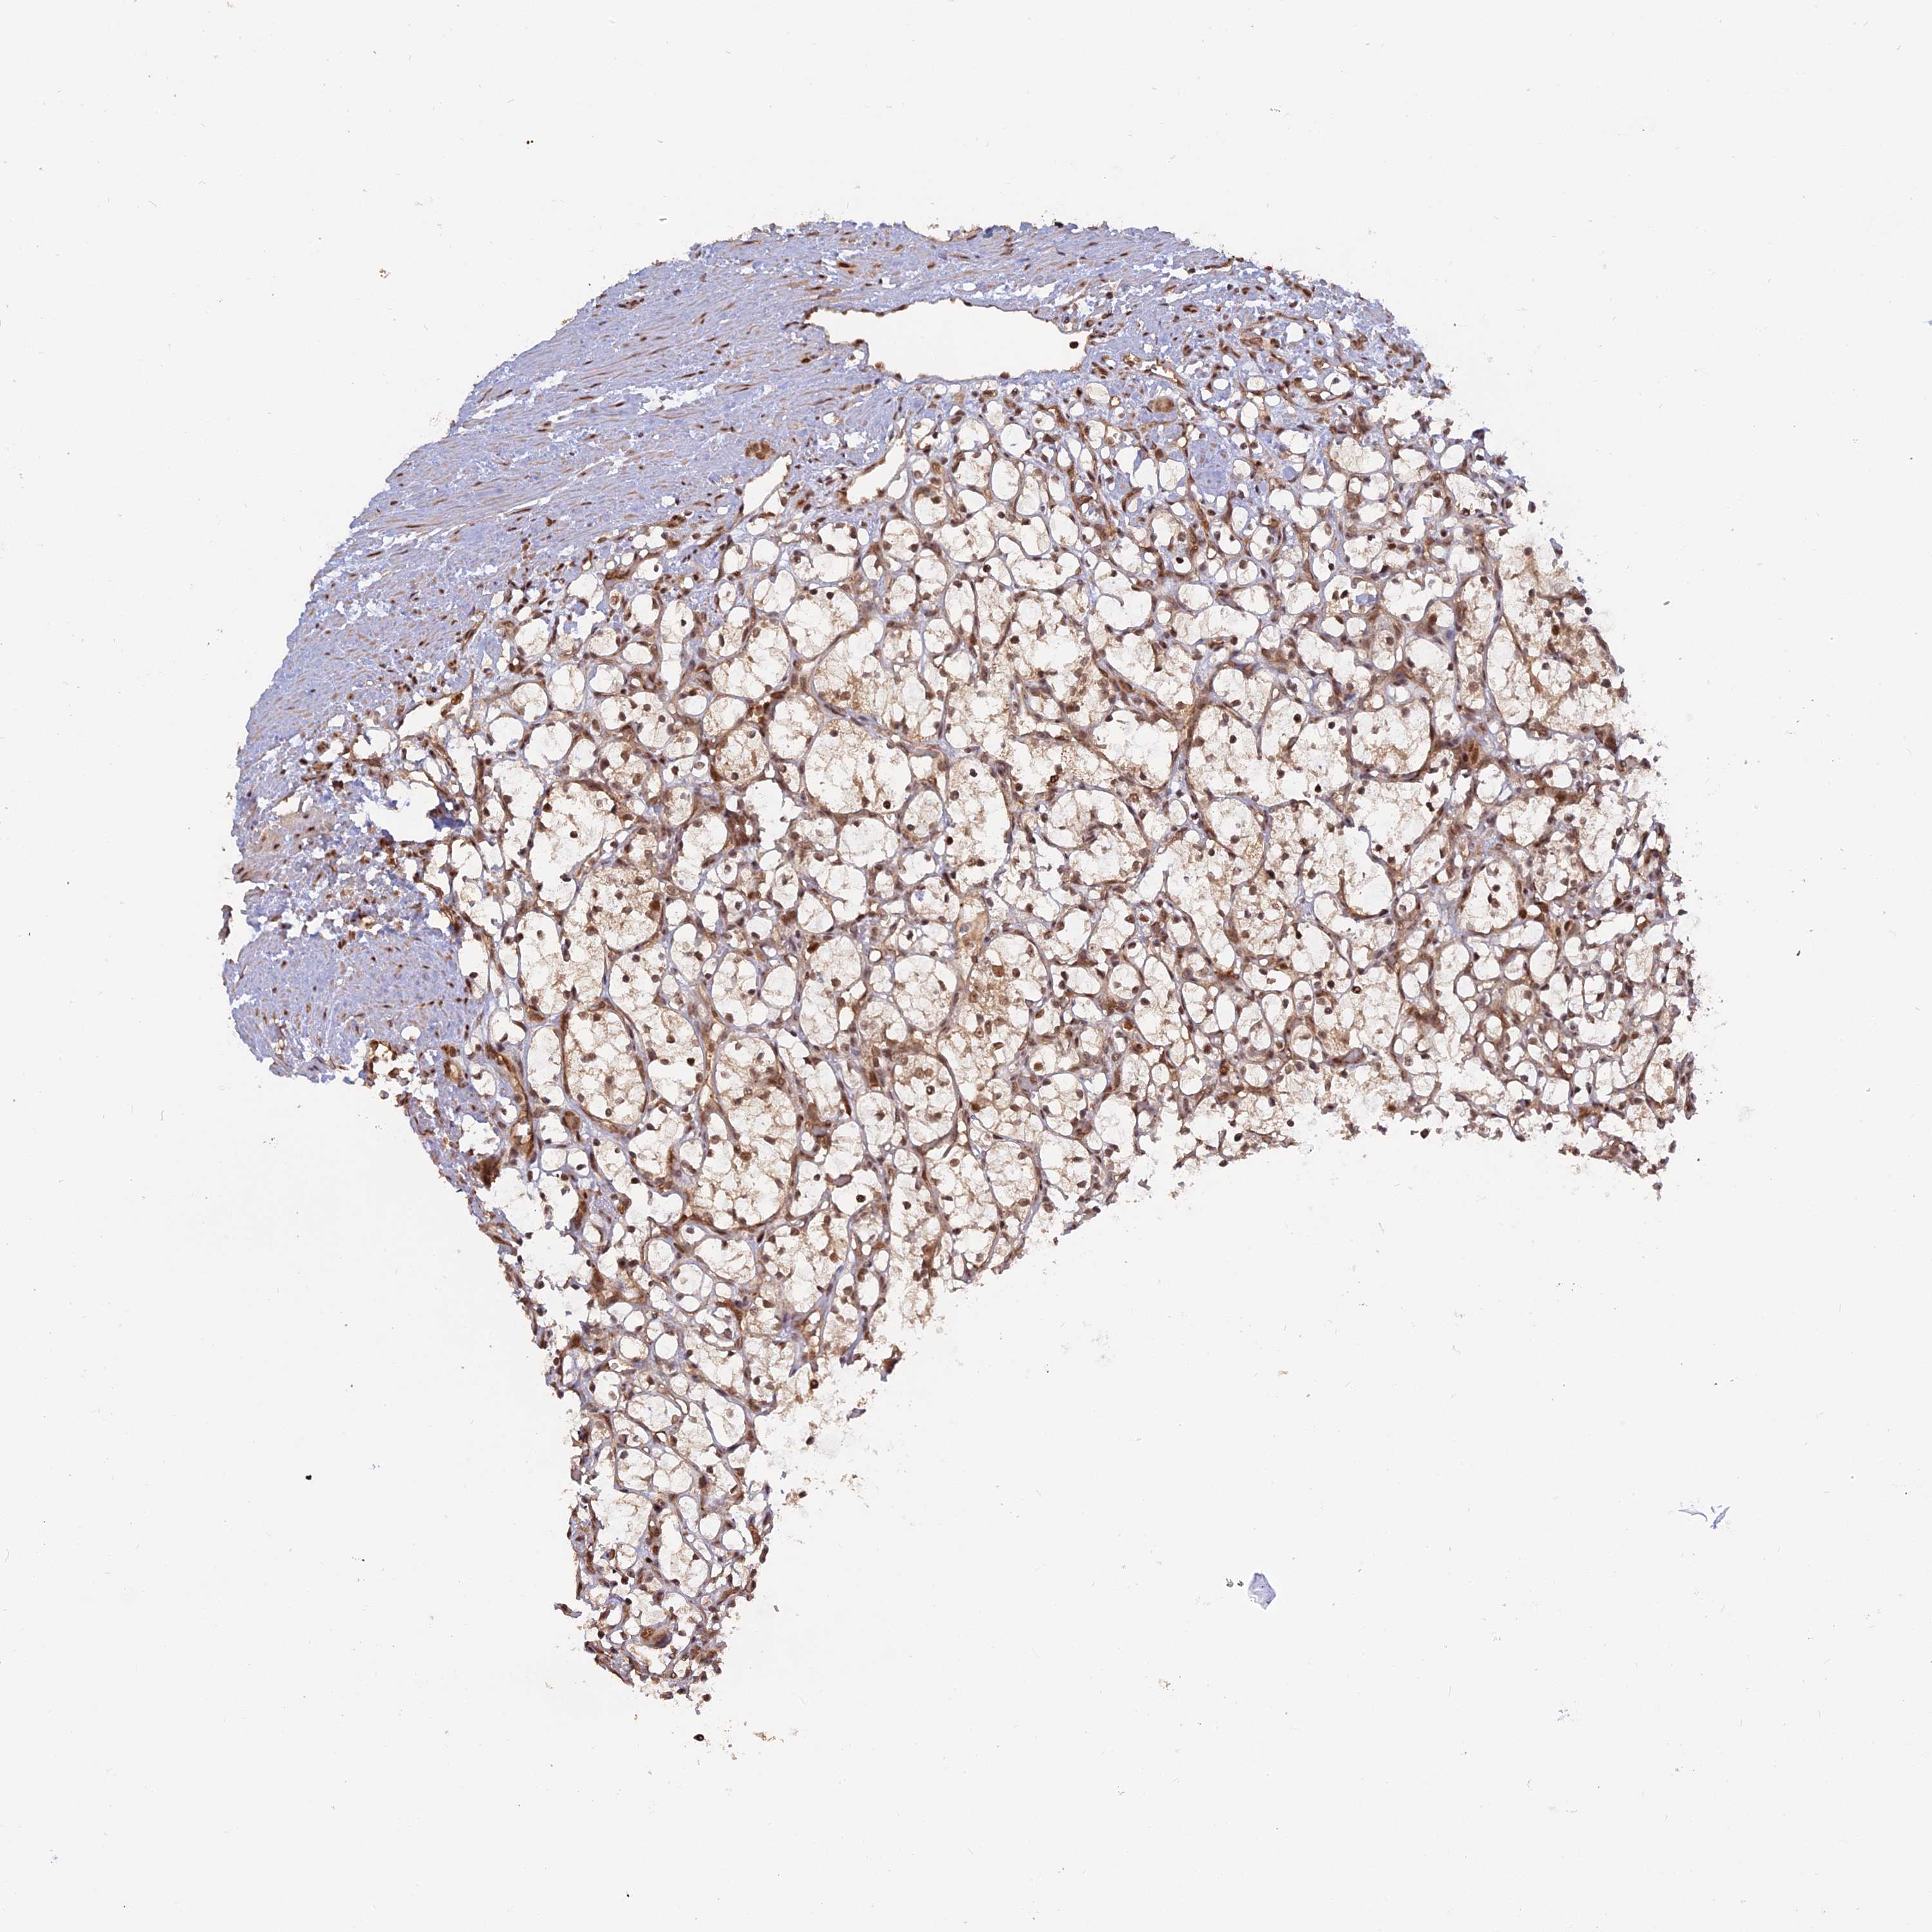

KIDNEY RENAL CLEAR CELL CARCINOMA (TCGA) - Interactive survival scatter ploti

The Survival Scatter plot shows the clinical status (i.e. dead or alive) for all individuals in the patient cohort, based on the same data that underlies the corresponding Kaplan-Meier plots. Patients that are alive at last time for follow-up are shown in blue and patients who have died during the study are shown in red.

The x-axis shows the expression levels (FPKM) of the investigated gene in the tumor tissue at the time of diagnosis. The y-axis shows the follow-up time after diagnosis (years). Both axes are complimented with kernel density curves demonstrating the data density over the axes. The top density plot shows the expression levels (FPKM) distribution among dead (red) and alive patients (blue). The right density plot shows the data density of the survived years of dead patients with high and low expression levels respectively, stratified using the cutoff indicated by the vertical dashed line through the Survival Scatter plot. This cutoff is automatically defined based on the FPKM cutoff that minimizes the p-score. The cutoff can be changed by dragging the vertical line or by entering a cutoff value in the square labeled "Current cut-off".

Under the Survival Scatter plot the p-score landscape (black curve; left axis) is shown together with dead median separation (red curve; right axis). Dead median separation is the difference in median mRNA expression between patients who have died with high and low expression, respectively. It is calculated as follows: median FPKM expression of dead patients with high expression - median FPKM expression of dead patients with low expression. This is intended to aid the user in visually exploring custom cutoffs and the associated p-scores and dead median separation.

Individual patient data is displayed and can be filtered by clicking on one or more of the category buttons on the top of the page. Categories describing expression level and patient information include: high, low, alive, dead, female, male and tumor stages. The scale of the x-axis can be toggled between linear and log-scale by clicking on the "x log" button. Mouse-over function shows TCGA ID, patient information and mRNA expression (FPKM) for each patient.

& Survival analysisi

Kaplan-Meier plots summarize results from analysis of correlation between mRNA expression level and patient survival. Patients were divided based on level of expression into one of the two groups "low" (under cut off) or "high" (over cut off). X-axis shows time for survival (years) and y-axis shows the probability of survival, where 1.0 corresponds to 100 percent.

PKIG is validated prognostic, high expression is favorable in Kidney Renal Clear Cell Carcinoma (TCGA)

Best expression cut offi

Based on the FPKM value of each gene, patients were classified into two groups and association between prognosis (survival) and gene expression (FPKM) was examined. The best expression cut-off refers the FPKM value that yields maximal difference with regard to survival between the two groups at the lowest log-rank P-value. Best expression cut-off was selected based on survival analysis .

When clicking on this number, the vertical dashed line indicating cut-off, the interactive survival plot, and the Kaplan-Meier curve will be adjusted to show results based on the best expression cut-off.

: 90

Average pTPM 91.0

Number of samples 521